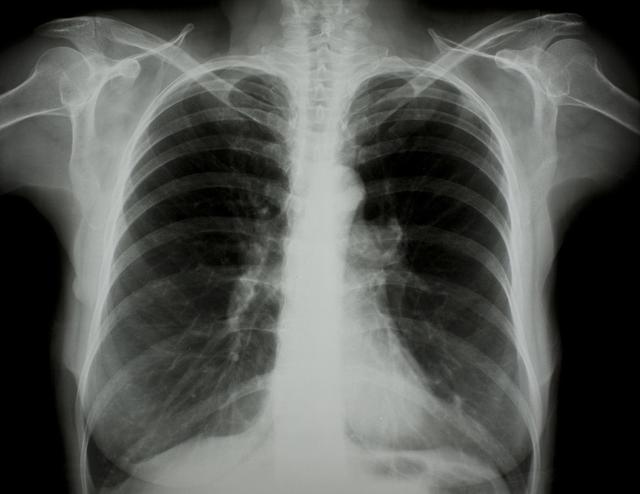

涪陵地區(qū)最新肺炎情況顯示,疫情形勢嚴峻。目前,當?shù)卣歪t(yī)療部門正在積極應對,采取一系列措施控制疫情傳播。具體感染人數(shù)、癥狀表現(xiàn)、疫苗接種情況等仍在持續(xù)更新中。請廣大市民密切關(guān)注官方發(fā)布的信息,做好個人防護,共同抗擊疫情。涪陵地區(qū)肺炎疫情嚴峻,政府積極應對,請市民關(guān)注官方信息,加強個人防護。

據(jù)最新官方數(shù)據(jù)顯示,涪陵地區(qū)肺炎病例數(shù)量令人擔憂,截至目前,涪陵地區(qū)累計確診肺炎病例XX例,疑似病例XX例,請大家務必提高警惕,不可掉以輕心。